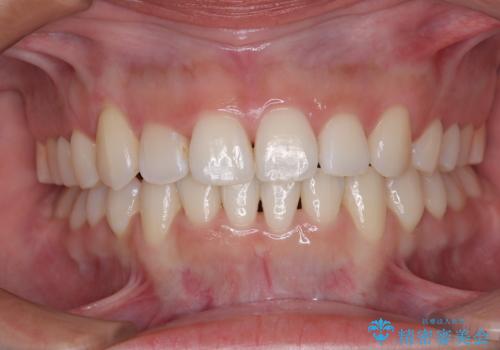

歯肉の腫れた前歯 部分矯正と歯周外科後の審美治療

抜歯や矯正治療、歯周外科処置など盛りだくさんの治療計画となったため、初めはとても不安に感じていらっしゃいましたが、矯正治療により八重歯が改善したり、下の歯が見えるようになったりとしたことで、途中からは治療結果を楽しみに感じていただけるようになりました。

矯正治療や歯周外科により治療期間は多少長くかかりましたが、患者様が望まれた前歯の仕上がりとなり、大変満足していただきました。